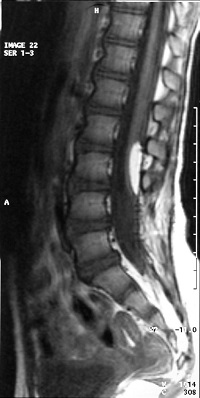

La espina bífida abierta prácticamente ya no se ve, y son el mielomeningocele, el meningocele y el mielocele. El tratamiento preventivo antes del embarazo (3 meses) y durante el embarazo (3 primeros meses) ha hecho que desaparezcan: de cualquier forma cuando ocurre, en nuestra opinión el tratamiento es la intervención quirúrgica.

La espina bífida oculta está formada por las malformaciones como los lipomas, senos dérmicos, diastematomielia, etc. que anclan la médula. Se operan con técnicas microquirúrgicas antes del año de vida.